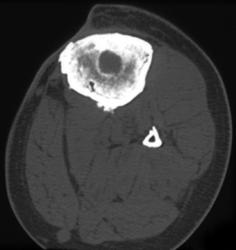

3D of Total Hip Replacement